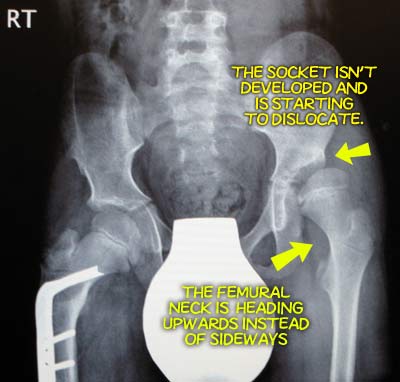

BEFORE

SURGERY